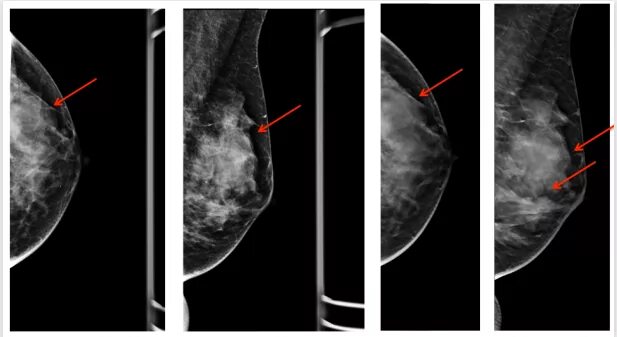

Линейный фиброз молочных